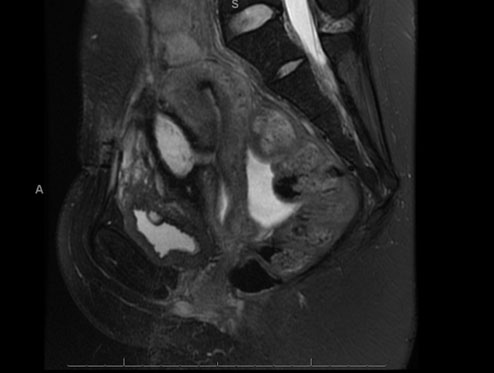

Ultrasound scan five days following the laparotomy showed complete resolution of the hematoma and she was discharged. Unfortunately, she represented to our Woman’s Assessment Unit on Day 11 post-relaparotomy with persistent pain and new vaginal bleeding. This was felt to be menstruation given she was seven weeks postpartum and not breastfeeding, however in view of the persistent pain an MRI was advised. Magnetic resonance imaging showed a persistent 8 mm dehiscence in the lower uterine segment causing a uteroperitoneal fistula to an adjacent small collection measuring 6 cm (Figure 3).

Figure 3: MRI, sagittal plane, T2 weighted image, showing uteroperitoneal fistula and preuterine hematoma.